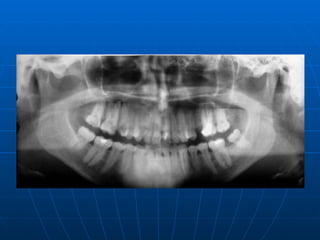

RADIOGRAFIA PANORAMICĂ A ÎNTREGII

DENTIŢII (ORTOPANTOMOGRAFIA)

   reprezintă obţinerea pe un film a imaginii desfăşurate a întregii

dentiţii

• tipuri de aparate

   aparate la care sursa de radiaţii este introdusă în gura pacientului

în centrul cercului imaginar înscris în potcoava maxilarului; din

acest punct se emit radiaţiile X de-a lungul razelor cercului

venind dinăuntru în afară şi impresionează un film extraoral

aplicat pe tegumentul labiojugal d-a lungul arcadei de

radiografiat; pe film sunt proiectate elementele anatomice

întâlnite de radiaţii, mărite de volum şi uşor deformate.

   Ortopantomograful – are la bază deplasarea simultană şi

antagonică a tubului de radiaţii situat în spatele capului

pacientului şi a unui film de 15/30 într-o casetă

semicirculară situat în faţa pacientuluimişcarea fiind

astfel reglată încât să se realizeze o măturare a întregii

dentiţii – expunerea durează în medie 15 secunde iar pe

film se proiecteazăarticulaţiile temporomandibulare,

întreaga dentiţie, sinusurile maxilare, fosele nazale şi

mandibula în întregime – flow-ul de mişcare scade

netitatea elementelor de structură osoasă